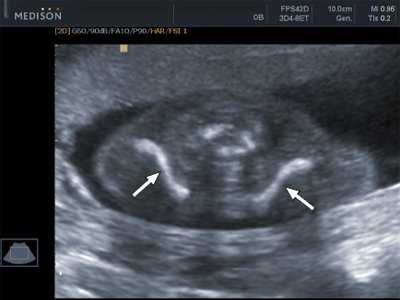

Основную роль в определении кампомелической дисплазии играют методики пренатальной диагностики: ультразвуковое исследование, кариотипирование и молекулярно-генетические анализы. Ультразвуковыми методами данное заболевание можно выявить уже со 2-го триместра вынашивания ребенка, ведущими проявлениями будет искривление костей конечностей, наличие 11-ти пар ребер и колоколообразная форма грудной клетки. Также могут определяться пороки развития черепа, лица, сердца и почек, гипоплазия лопаток и тел позвонков, увеличение размеров тазового отверстия. На основании перечисленных данных пренатального ультразвукового исследования можно обоснованно предположить наличие кампомелической дисплазии и поставить вопрос о прерывании беременности по медицинским показаниям.